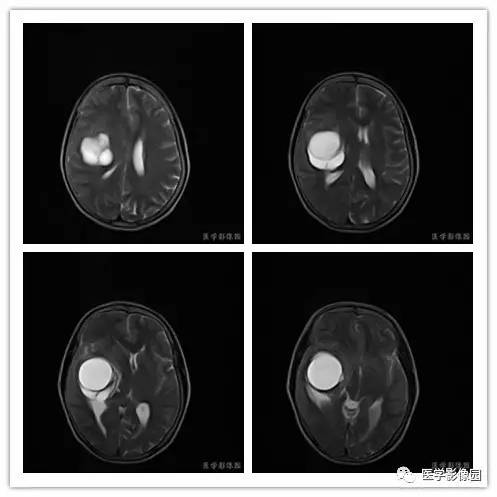

影像学表现:右侧颞叶深部区见一长T1、长T2囊样信号,成明显环形强化、未见明确结节影,没有FLAIR和DWI图,内见分隔,边界较清,周围水肿不明显,右侧脑室明显受压、颞角扩大,右侧脑沟明显变浅,脑中线结果向左偏移。

1.肿瘤主要表现为等长T1 、等长T2 混杂信号影,偶可见短T1 或短T2 信号影,注药后,肿瘤增强明显但不均匀;